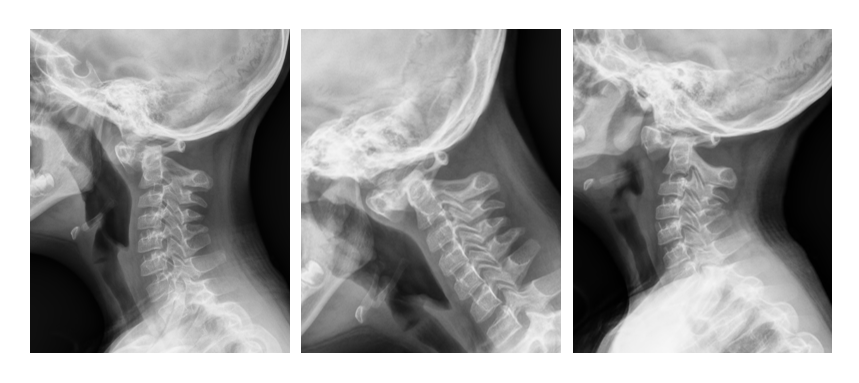

近日,西安市红会医院脊柱病医院许正伟主任的诊室,迎来了一位特殊的小患者—— 8 岁的唐氏综合征患儿康康(化名)。康康母亲满脸焦虑:孩子最近总是拿手抱着脖子,玩耍时也小心翼翼。经详细检查,一个隐藏在颈椎最深处的危险被揭示:寰枢椎完全脱位(图一)。这如同在生命中枢的「枢纽」上发生了致命偏移,随时可能压迫脊髓,导致瘫痪乃至呼吸心跳骤停。

面对挑战,许正伟主任团队在西安市红会医院脊柱病医院院长闫亮、学科带头人贺宝荣主任带领下,为康康制定了周密的个性化方案。术前,三维椎动脉 CTA 精准「测绘」出脱位的详情与椎动脉的走向(图二及图三)。由于患儿无法配合常规牵引,团队决定在术中实施高难度的颅骨牵引复位。